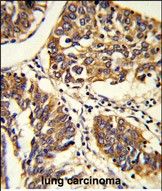

Applikationen WB, IHC-P

IHC-P: 1:50~100